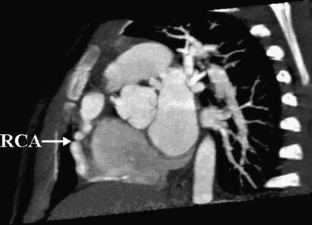

MSCT showed coronary artery injury in 15 of the 48 children. Among these 15 children, 20 coronary artery branches showed complications, including the left coronary artery branches in 15 (31.2%) and the right coronary artery branches in 5 (10.4%). Complications in the left coronary artery branches included dilation in 12 (25.0%) and stenosis, calcification and the combination of the two in one each, and the right coronary artery branches showed dilation; two branches also showed beaded changes. MSCT also showed dilation in the left anterior descending arteries in two children. These children showed no abnormality on 2-D echocardiography.

Fig. 1